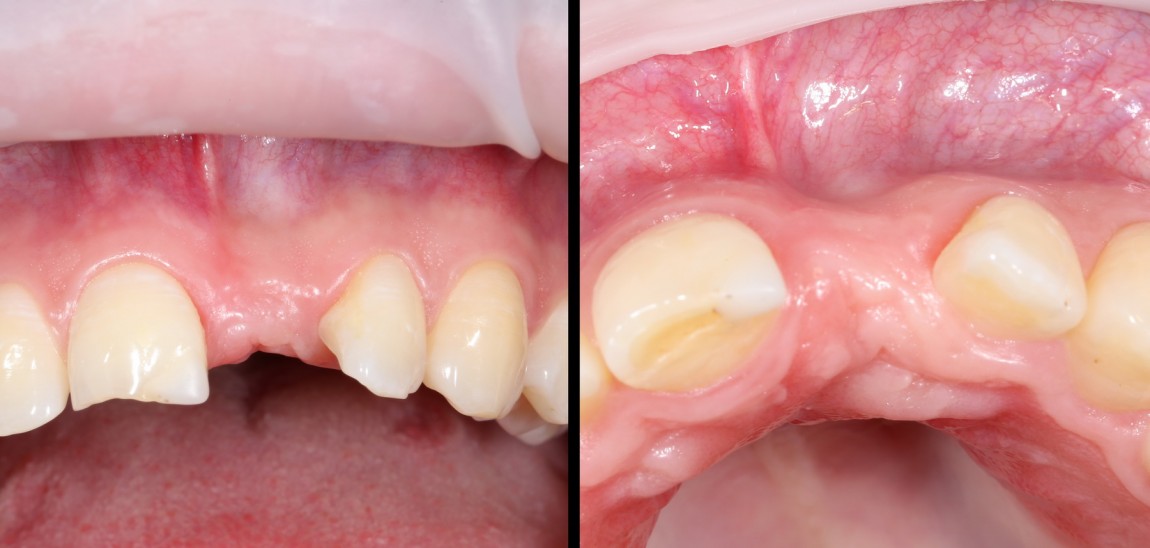

Через год после травмы, девушка обратилась в нашу клинику для восстановления отсутствующего зуба. К тому моменту у нее уже был временный съемный протез, изготовленный в вышеозначенном стоматологическом кабинете, ну и, вот какая клиническая картина:

Хочу спросить вас, уважаемые друзья, можно ли в таком состоянии и при таких объемах альвеолярного гребня поставить имплантат в область отсутствующего зуба? Безусловно, можно. Для этого нужно просто взять имплантат потоньше и поставить его подальше, в сторону неба — и он нормально интегрируется.

Возможно ли получить на подобном импланте более-менее приемлемый эстетический и функциональный результат? Вряд ли. Если за пределами эстетически значимой зоны мы можем пойти на эстетические компромиссы (все равно никто не увидит), то проблемы с эстетикой в области передней группы зубов… да еще у девушки…. так можно человеку всю личную жизнь испортить.

Поэтому, несмотря на возможность установить имплантат потоньше и подальше, мы планируем в ходе имплантологического лечения увеличение объема альвеолярного гребня до приемлемого уровня с помощью остеопластических процедур. Ориентиром «приемлемого уровня» является симметричный центральный резец. В идеале, вокруг нашего импланта должен быть абсолютно такой же объем тканей — только так мы можем добиться эстетического результат лечения.